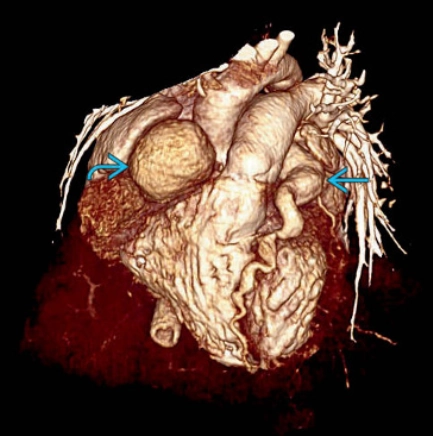

Phình động mạch vành (Coronary artery aneurysm)